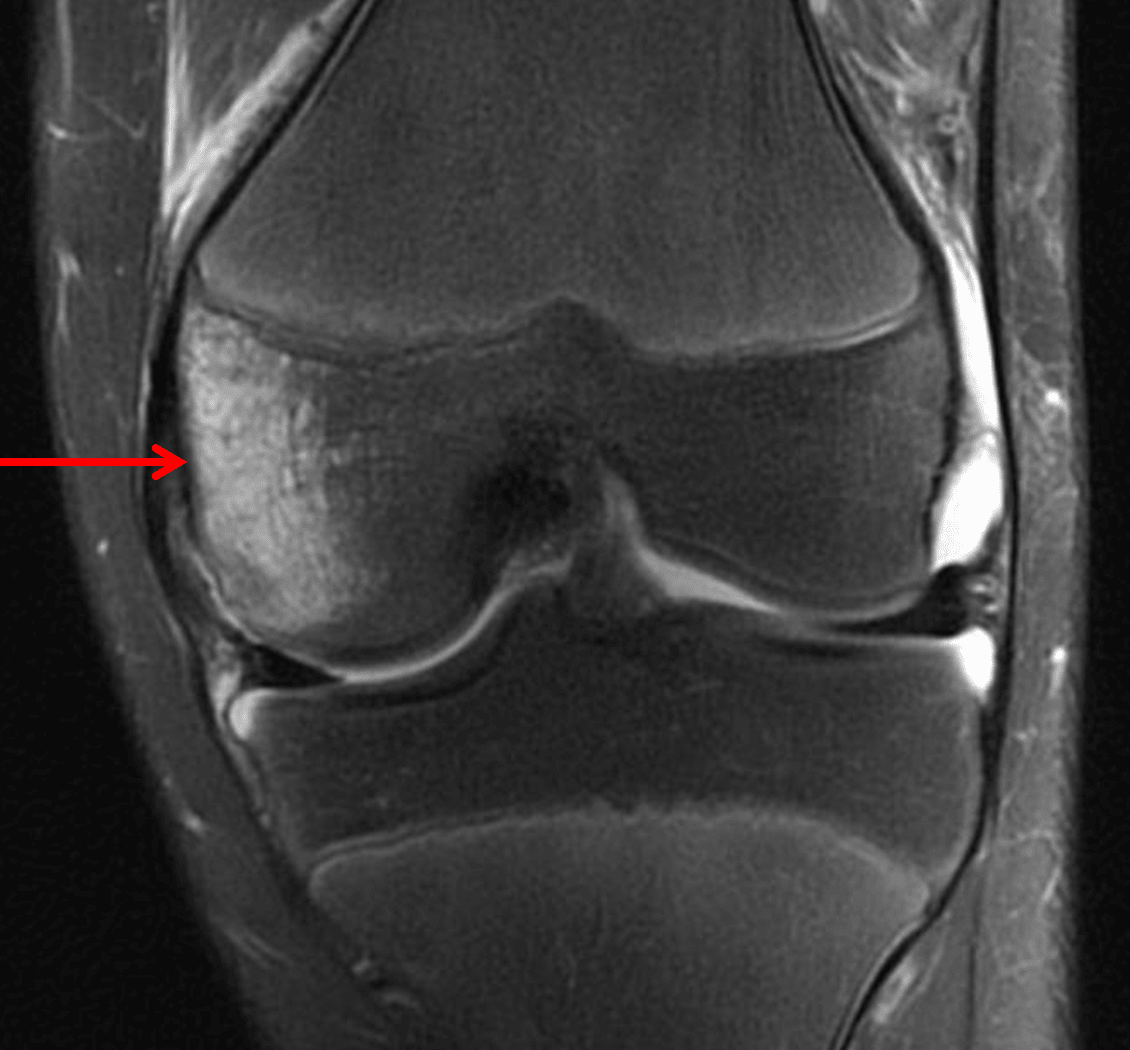

Followup knee MRI in this patient shows a large medial femoral condyle bone contusion without clear fracture line.